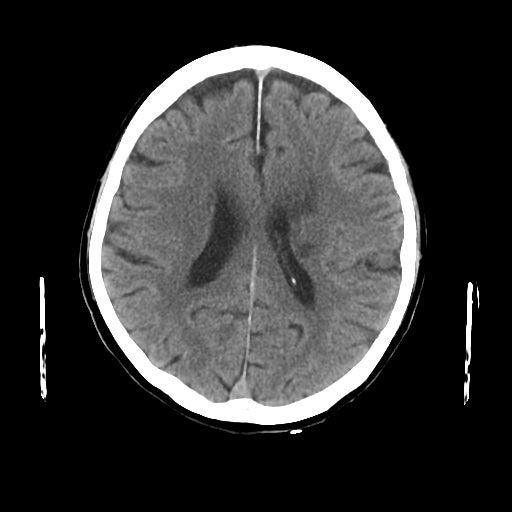

2-1. 低吸収領域の検出・表示例(下)

頭部CT検査において、周囲に比べ白く映る部分(高吸収領域)が見られる場合には、脳出血が疑われます。脳出血は高血圧・脳腫瘍・脳血管の異常などが要因となり、脳の動脈が破れて脳内部に出血した状態を指します。一方、周囲に比べ黒く映る部分(低吸収領域)が見られる場合には、脳梗塞が疑われます。脳梗塞は、脳内の血管が詰まるなどにより血液の流入が止まり、脳に酸素や栄養が行き渡らなくなる状態です。また、急性期の脳梗塞では、頭部CT検査において、灰白質と白質の境界が消失するなどの所見(ECS=early CT sign)が見られ(2)、こうした所見を見落とさずに治療につなげることが肝要です。